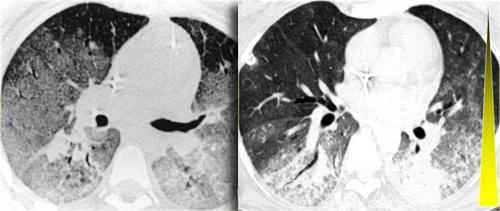

Bên trái là hình ảnh CT có tiêm thuốc cản quang của một bệnh nhân viêm phổi tăng bạch cầu ái toan mạn tính.

Lưu ý phân bố ngoại vi của các vùng đông đặc.

Các hình ảnh bên trái cho thấy sự tương đồng giữa viêm phổi tăng bạch cầu ái toan mạn tính và viêm phổi tổ chức hóa.

Việc phân biệt hai bệnh lý này cần dựa trên các dữ liệu lâm sàng và xét nghiệm.